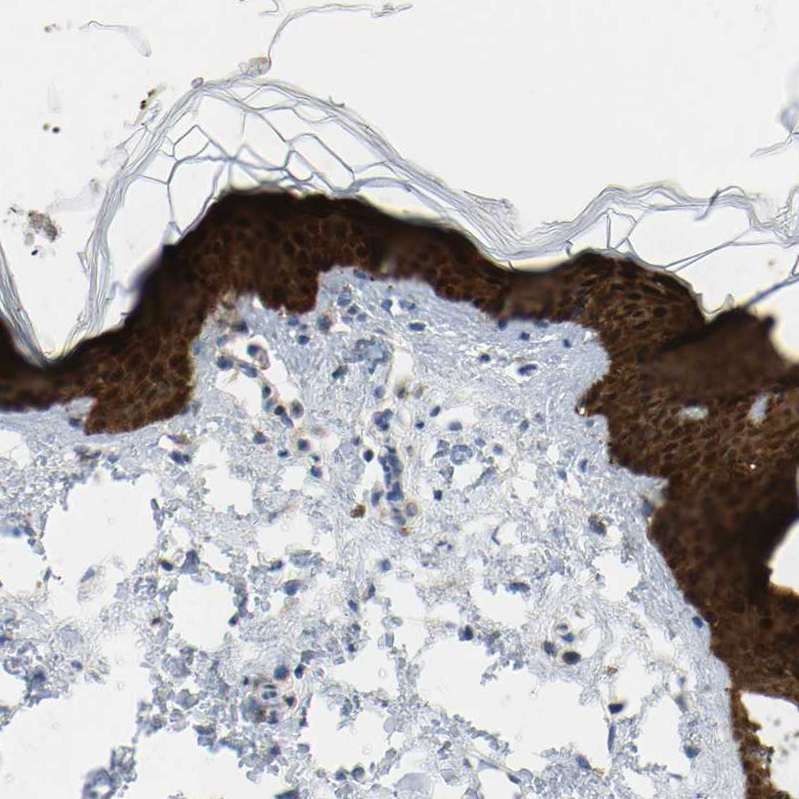

Immunohistochemistry analysis in human skin and skeletal muscle tissues using HPA019025 antibody. Corresponding SERPINB5 RNA-seq data are presented for the same tissues.